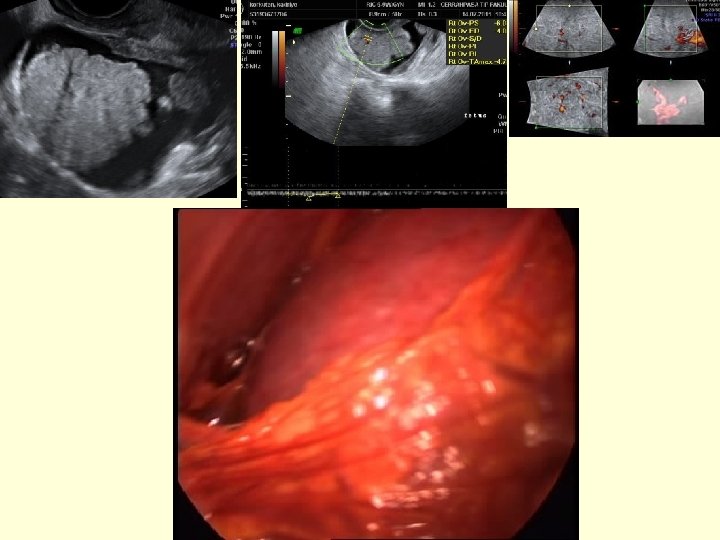

papillary projections

Frozen –section evaluation

Malignant masses